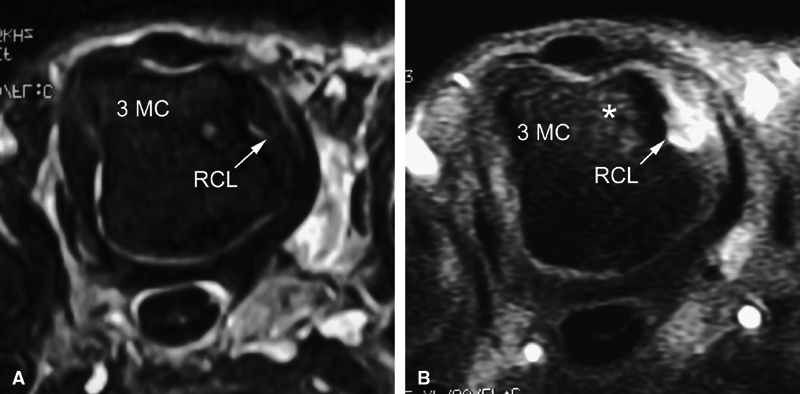

Intravenous injection of gadolinium may increase image contrast, making it possible to visualize small ligament tears (Fig. 11.13).10 Tears may involve the distal or proximal insertion or the middle third of the ligament (Figs. 11.13 and Fig. 11.14).

-

FIGURE 11.13 ● Proximal tear of the radial collateral ligament (RCL) of the third metacarpophalangeal joint. Comparison of axial STIR (A) and post-contrast fat-suppressed T1-weighted image (B). Focal irregularity and slight hyperintensity of the RCL can be seen on the STIR image. Strong enhancement of the proximal part of the RCL and bone edema (asterisk) is seen on the T1-weighted images. MC, metacarpal.

|